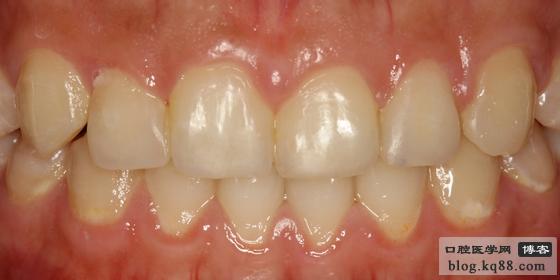

選用D6樹脂(選用4種樹脂)進(jìn)行修復(fù),此圖為打磨拋光后的即刻照片

一星期后的效果(微笑)樹脂有個(gè)過度的時(shí)期。